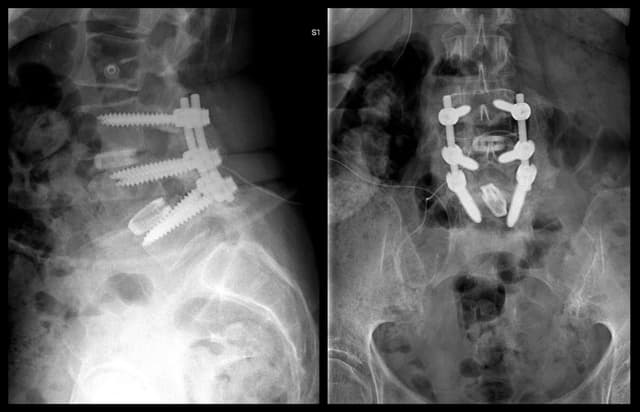

L3-4 TLIF

Pre-op

Post-op